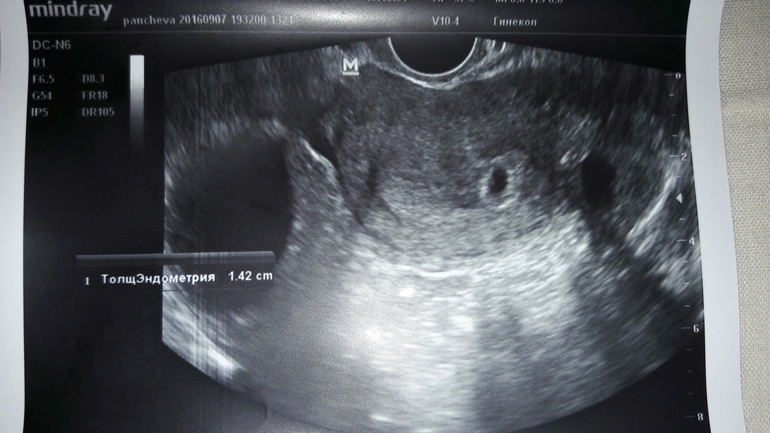

Результаты: УЗИ, КТГ, доплера, скринингаНас нашли пя 7 мм. Жт 15 мм. Киста есть с кровотоком аж 5*4 см. Так же нечто( ни кто не знает что это) возможно из-за этого кровит. Срок 4 недели и 2 дня( это эмбриональный?) А вот и нечто с права вытянутое.

Это акушерских скорее всего. А похоже на тонус, как будто расплющело. Ну или "криво" сфотографировали.